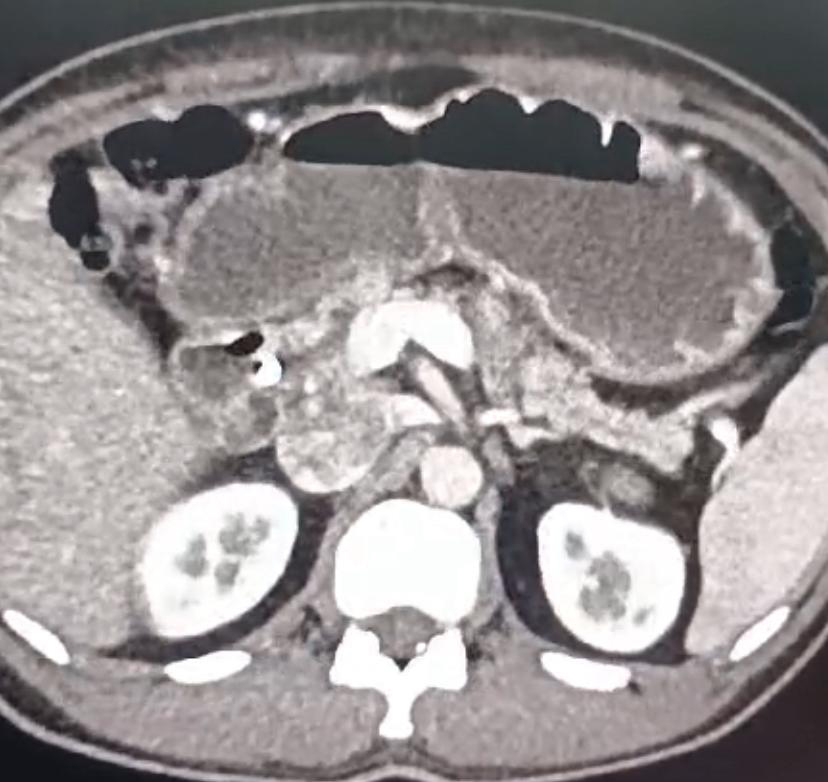

A 60 year old gentleman presented to us with obstructive jaundice due to a periampullary (ampullary) cancer. Patient already had a stent inserted in the bile duct for jaundice about 6 weeks prior at a rural center. The patient was fit for surgery and ideal for a laparoscopic Whipple, wherein the tumor is removed along with head of pancreas, entire duodenum, part of stomach & common bile duct. Patient underwent a laparoscopic Whipple surgery as planned and was discharged by 8th postoperative day.

Laparoscopic Whipple surgery is ideal in small tumors with dilated pancreatic and bile duct, without vascular involvement and without large lymph nodes.